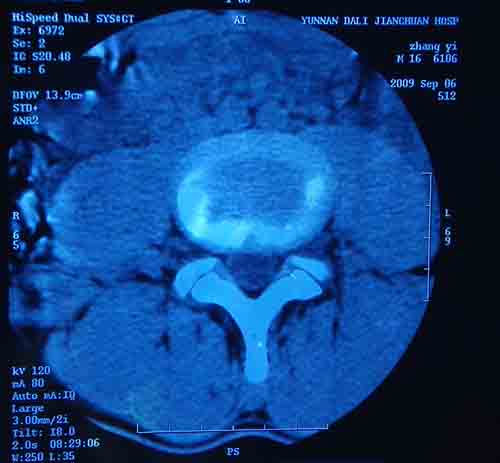

标题: CT22052:腰5/骶1椎间膨突出外,还有点异常,不知是什么东东 [打印本页]

标题: CT22052:腰5/骶1椎间膨突出外,还有点异常,不知是什么东东

腰5/骶1椎间膨突出外,还有点异常,不知是什么东东,请各位大虾帮忙看看(12骨窗最明显)

椎体后缘软骨结节